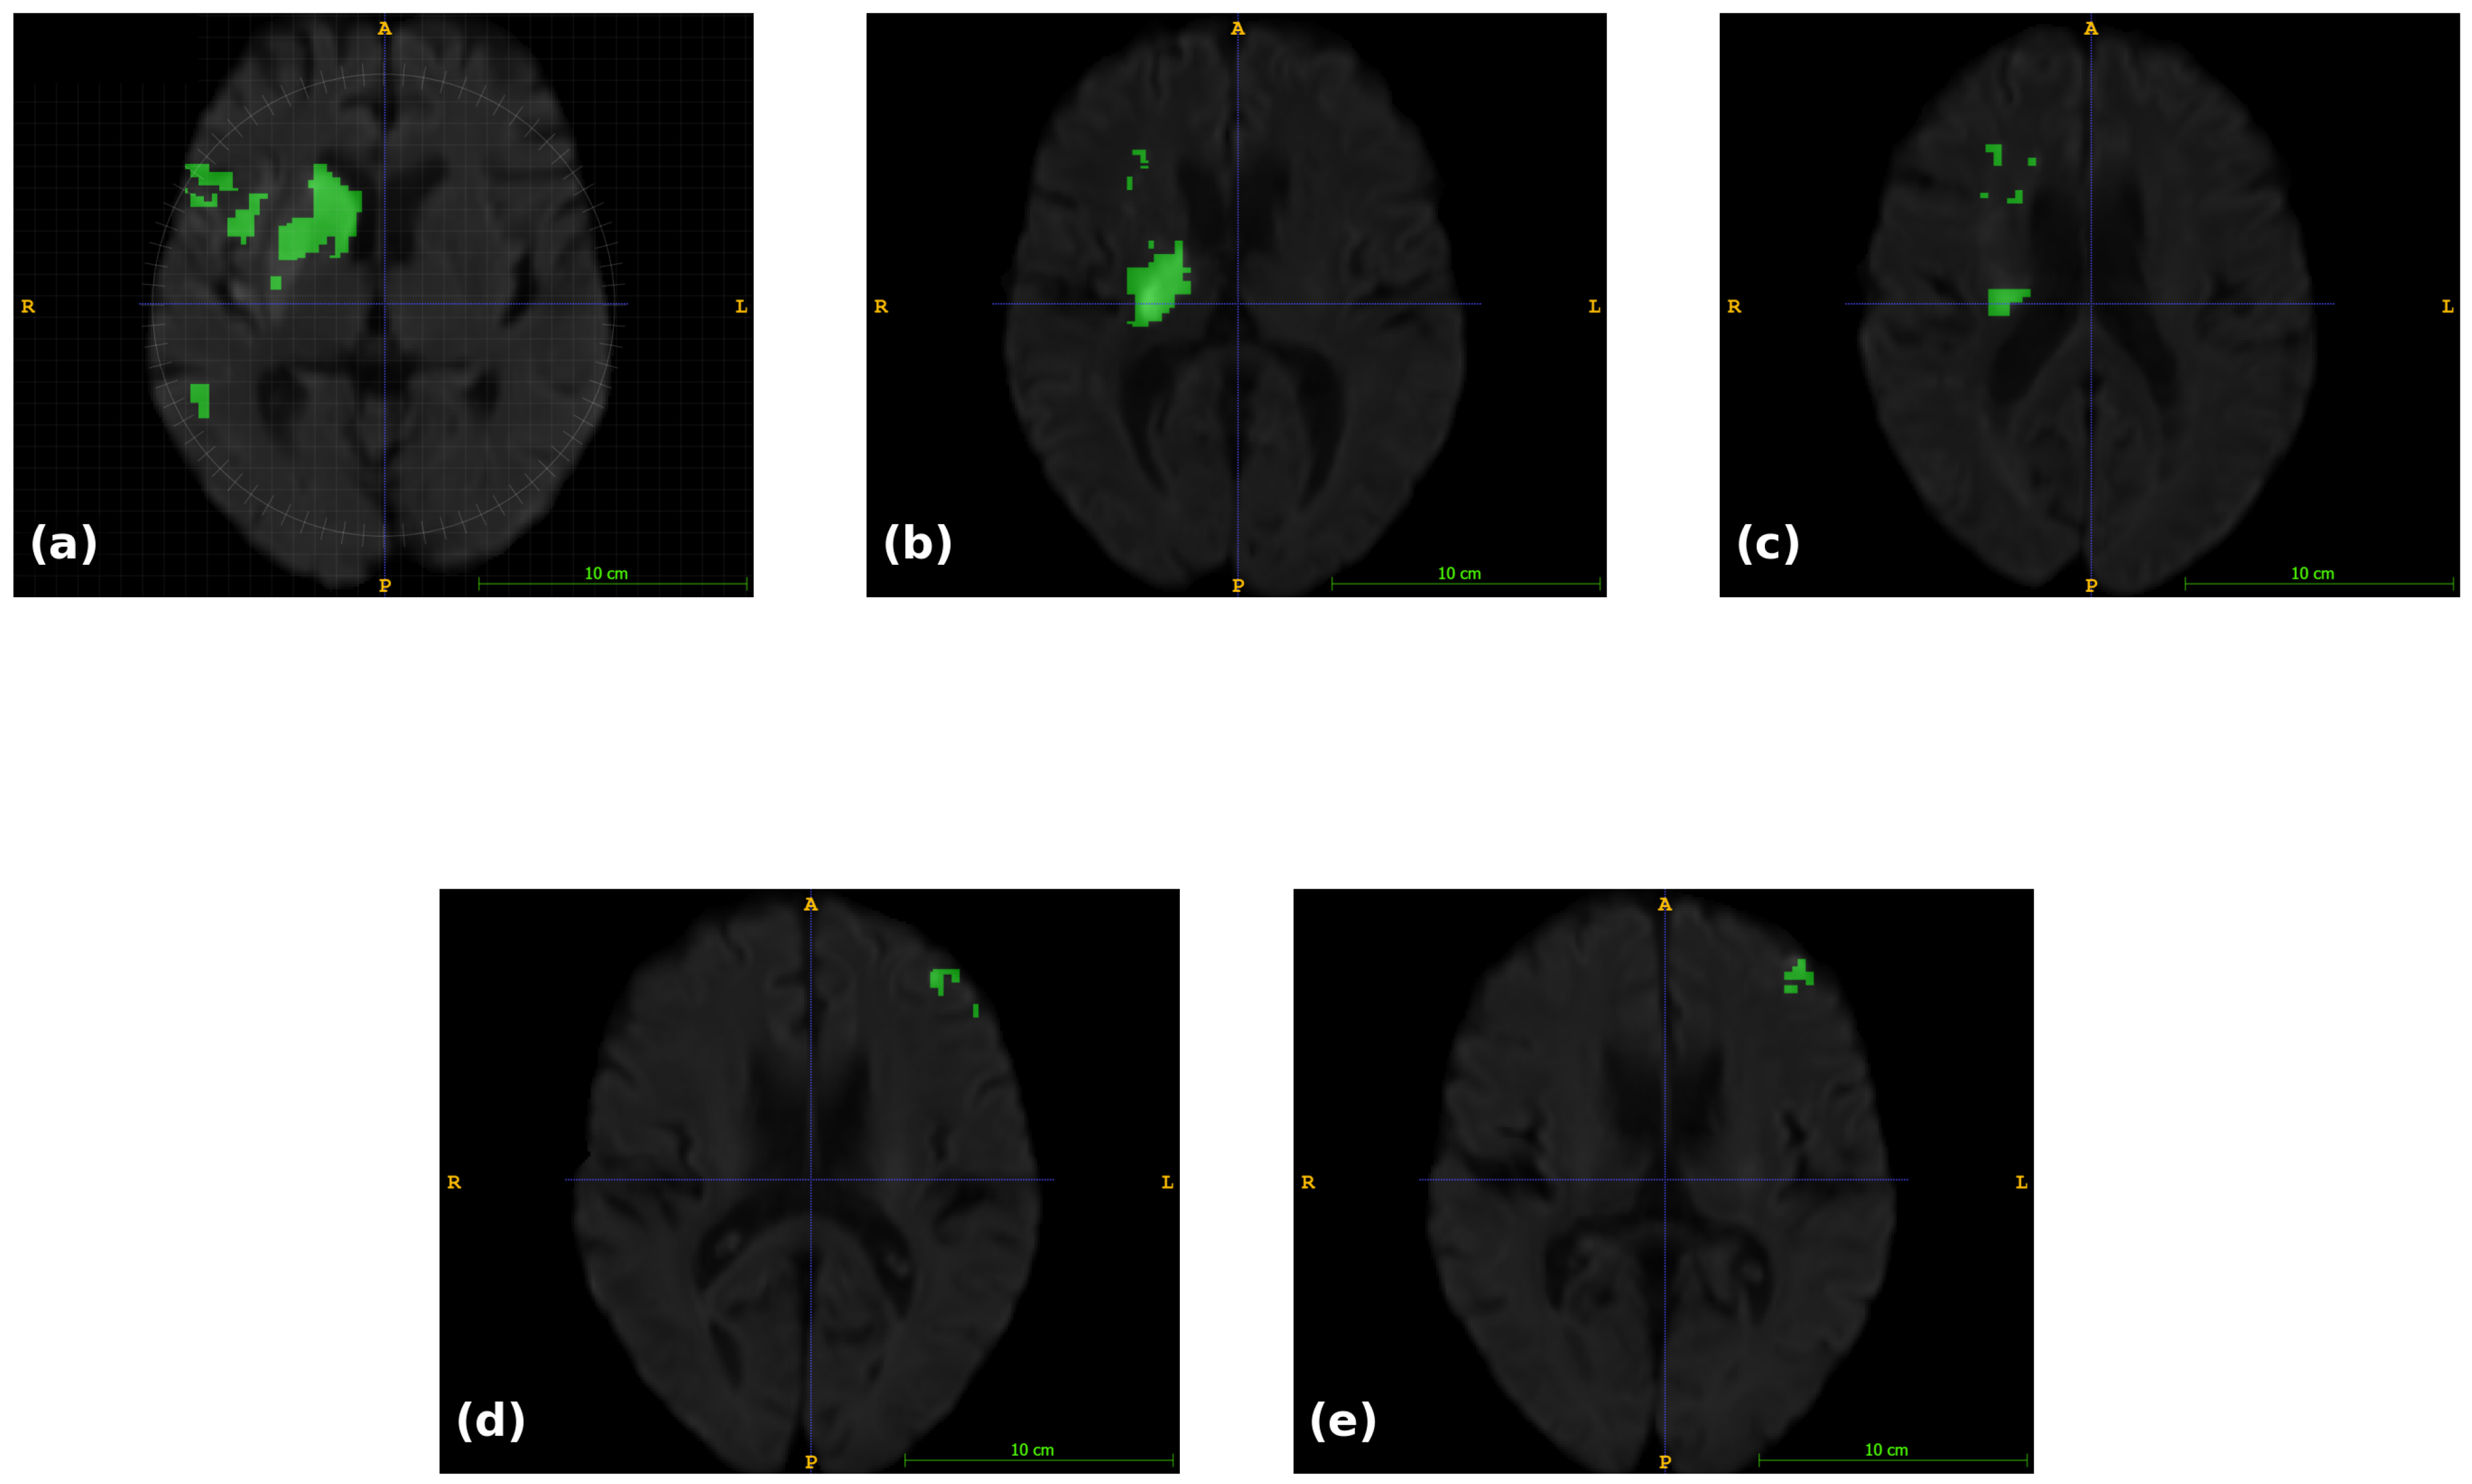

- Rahman, A.; Chowdhury, M.E.; Wadud, M.S.I.; Sarmun, R.; Mushtak, A.; Zoghoul, S.B.; Al-Hashimi, I. Deep learning driven segmentation of ischemic stroke lesions using multi-channel MRI. Biomed. Signal Process. Control 2025, 105, 107676. [Google Scholar]

| Rahman et al., 2025 [15] | 2025 | DWI, ADC, and eDWI | DenseNet121 encoder + SelfONN-CSCA (Channel and Spatial Compound Attention)-UNet decoder | DWI only: 83.88, DWI + ADC: 85.86, DWI + ADC + eDWI: 87.49 |